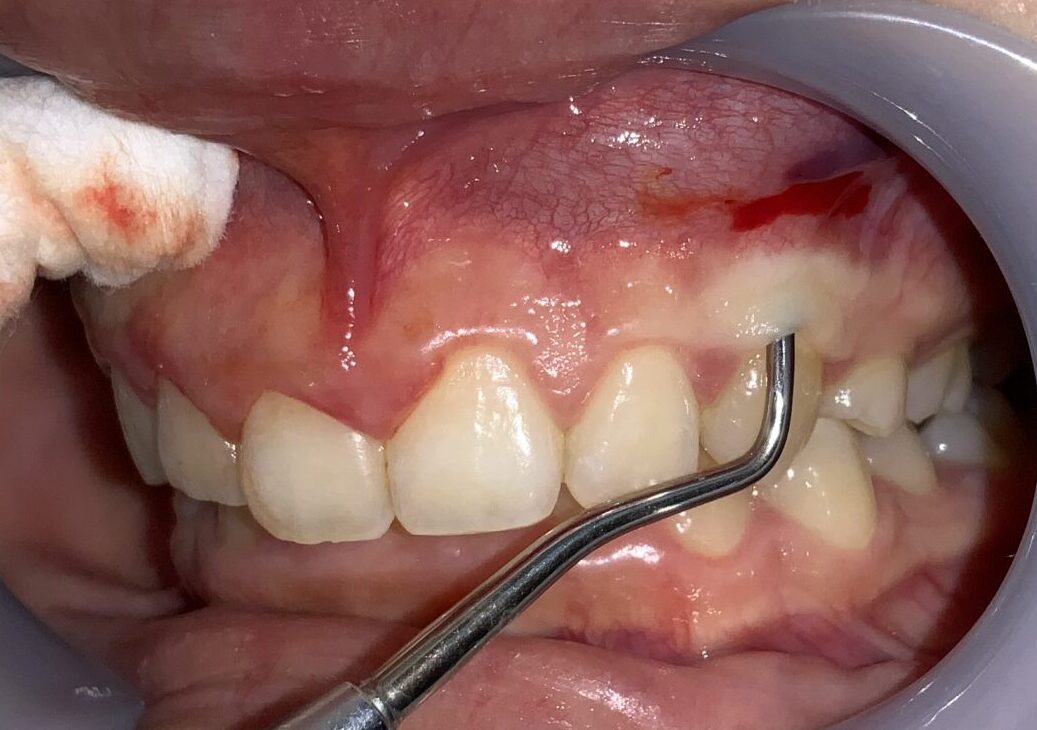

反対側の歯の検査に移動します。

血液が出ているのは、局部麻酔の影響です。歯の検査の影響ではありませんので、ご心配なく、検査をお受けください。

歯ぐきの厚みや歯槽骨の状態も確認します。

この歯も歯ぐきが被っている量が相当あります。